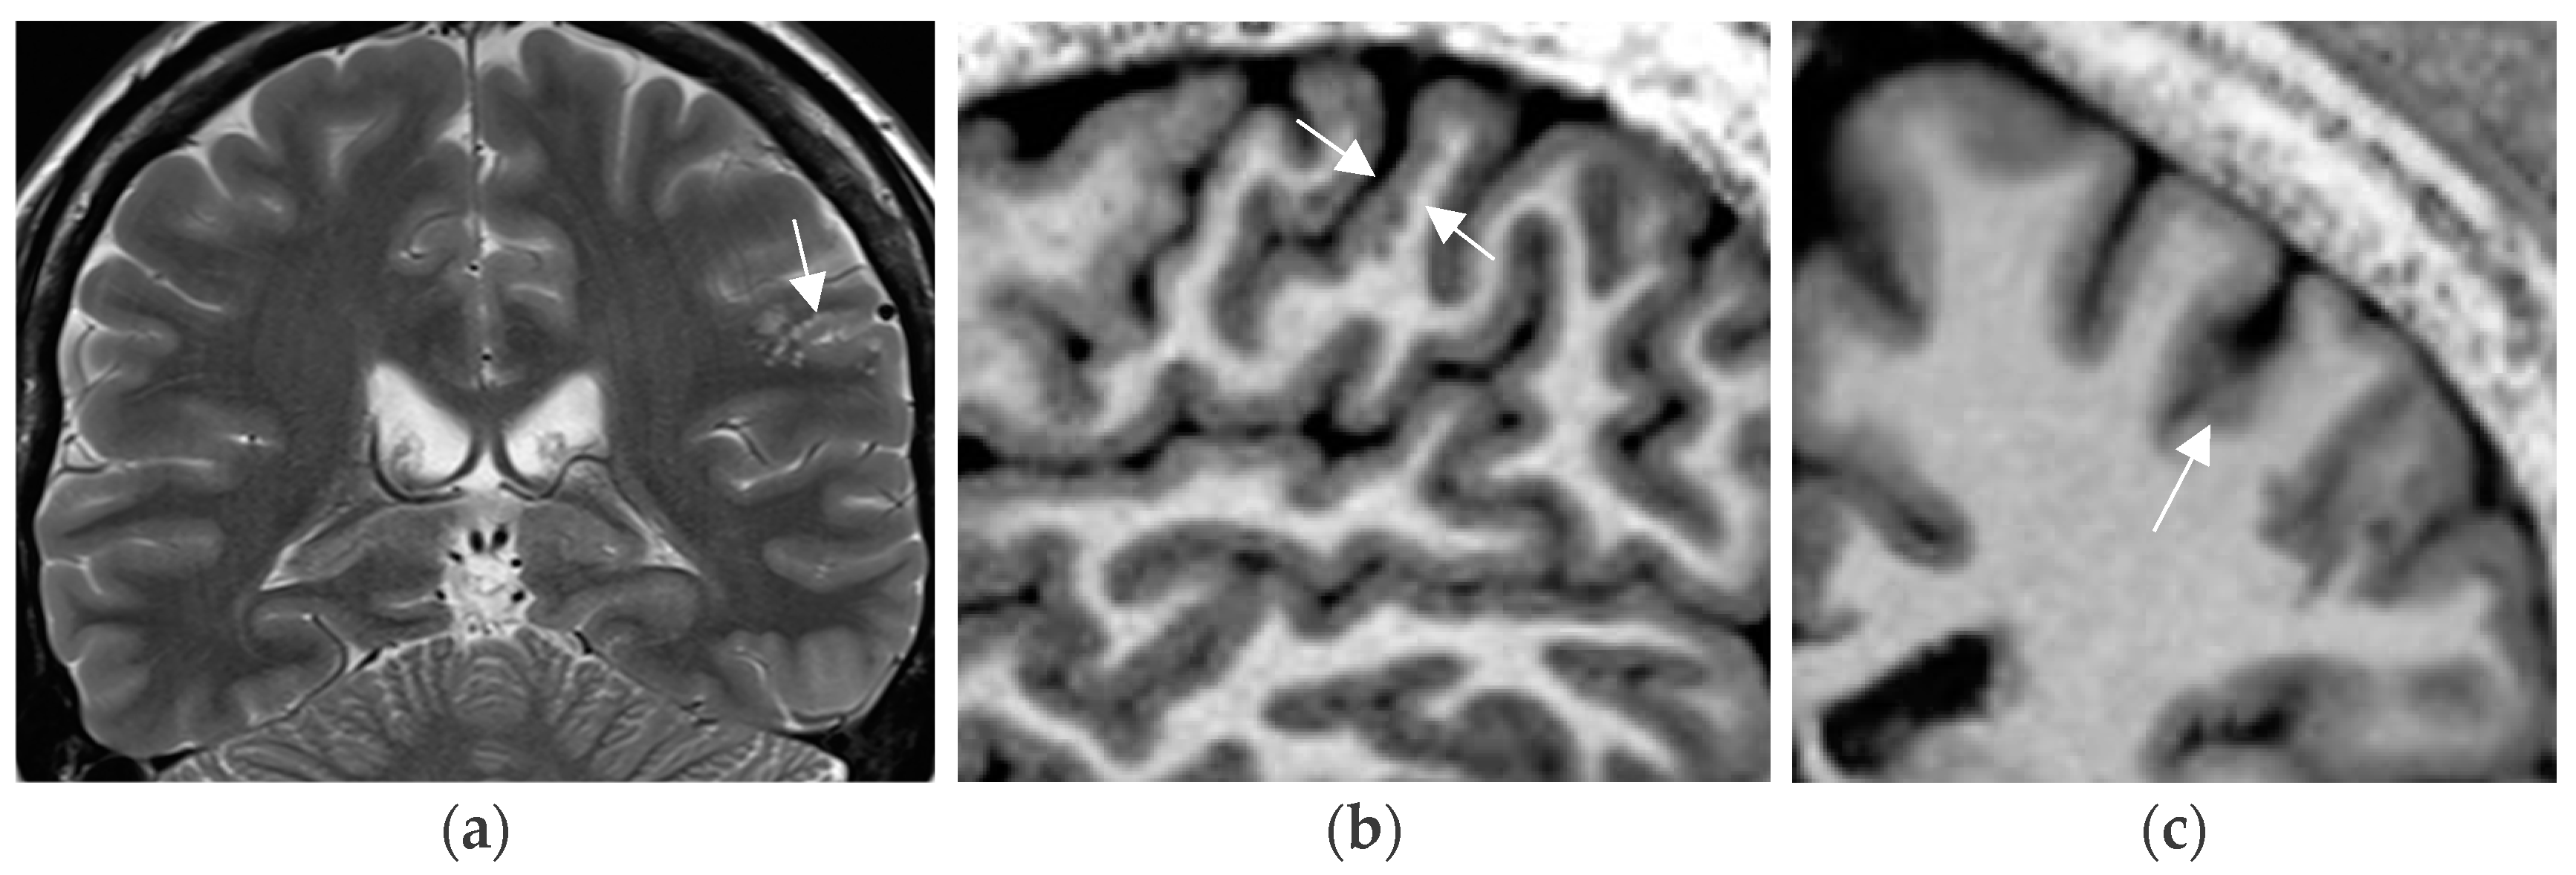

4.7. Postprocessing by Quantitative Analysis of Signal Intensity, Volumetry Enhances Temporal Lesion Identification

Coronal high resolution T2 weighted sequences and 3D Flair sequences are standard constituents of an epilepsy specific protocol to render visible hippocampal sclerosis, FCD type II, and areas of gliosis. Data postprocessing by MRI quantification relates to calculation of Flair and T2 signal (relaxometry) of the hippocampus and within lesions of the temporal lobe. Volumetry signifies quantification of the volume of the hippocampus and amygdala (Figure 7).

MR volumetry (a) and T2/FLAIR relaxometry (b): right hippocampal abnormality histologically verified as hippocampal sclerosis and gliosis as evidenced by a mild area decrease of the right hippocampus (0.78 cm2 versus 0.90 cm2) and a slight FLAIR signal elevation (245 vs. 217). Both findings were suspected visually but were verified by postprocessing of volume and signal intensity.

In 78 patients with temporal lobe epilepsy, T2 relaxometry identified lesions in an additional 15 patients (19%) with visually normal MRI and volumetry identified a further 10 cases (13%) of hippocampal sclerosis. The combination of T2 relaxometry and volumetry provided the highest yield with recognition of hippocampal sclerosis in 22 (28%) patients with previous normal interpretations [81]. However, contrary to hippocampal sclerosis, FCD type I lesions, despite postprocessing, still have a high association with MR interpretation as “nonlesional”.